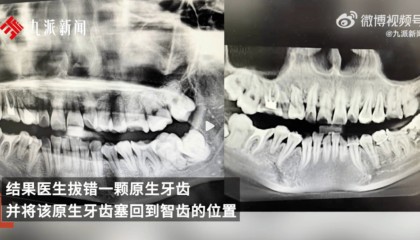

女子疑因拔错牙又被塞回坠楼身亡,多方回应

近日,一位网友发文称自己34岁妹妹在安徽安庆市立医院口腔科门诊拔智齿,结果医生拔错一颗原生牙齿,并将...